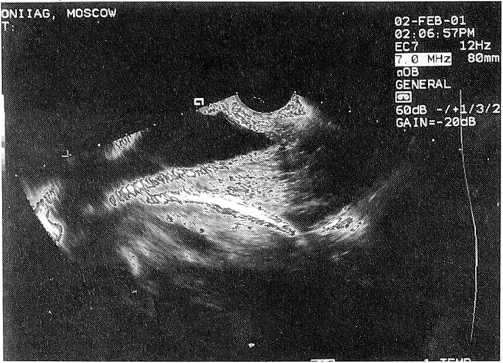

Мы располагаем случаями самопроизвольных родов при равномерной толщине рубца 3-4 мм (рис. 1) с хорошей его васкуляризацией. Кстати, такова толщина и интактного нижнего сегмента матки в конце беременности и в родах. Рубец же, где имеются локальные истончения, независимо от его общей толщины (рис. 2), по нашему мнению, является неполноценным.

Рис. 3. Анатомически неполноценный (неравномерной толщины) рубец на матке